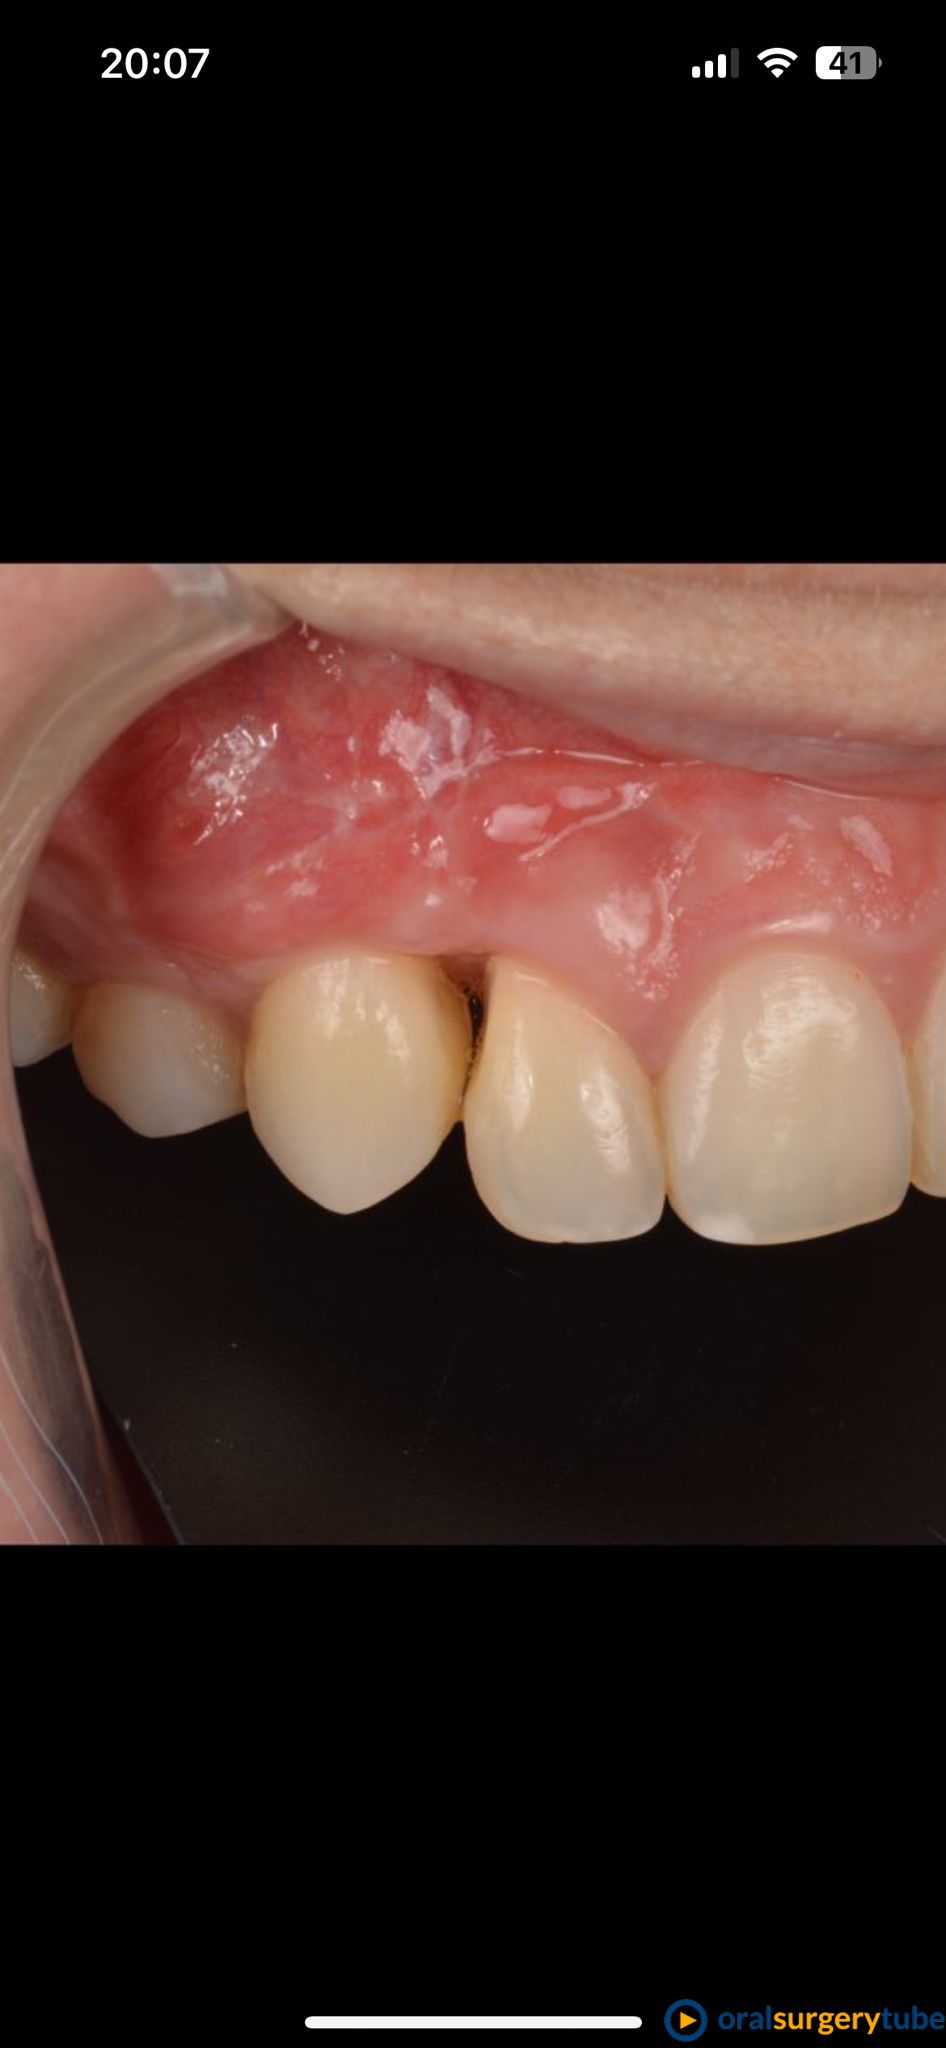

Seguimiento de caso de defecto vertical entre dos dientes (12 y 13) tras cirugía ortognática.

Paciente de mediada edad que es remitida para intentar mejorar el estado periodontal de los dientes 12 y 13 tras cirugía ortognática. A la paciente le habían realizado previamente varios injertos de tejido conectivo y empleo de Emdogain® sin éxito. Se plantea hacer técnica de Wall technique de Zucchelli modificada para simultanear técnicas de regeneración ósea guiada.

Bueno, me hubiera encantado poder cubrir toda la recesión, pero creo que hemos llegado al máximo que se podía.